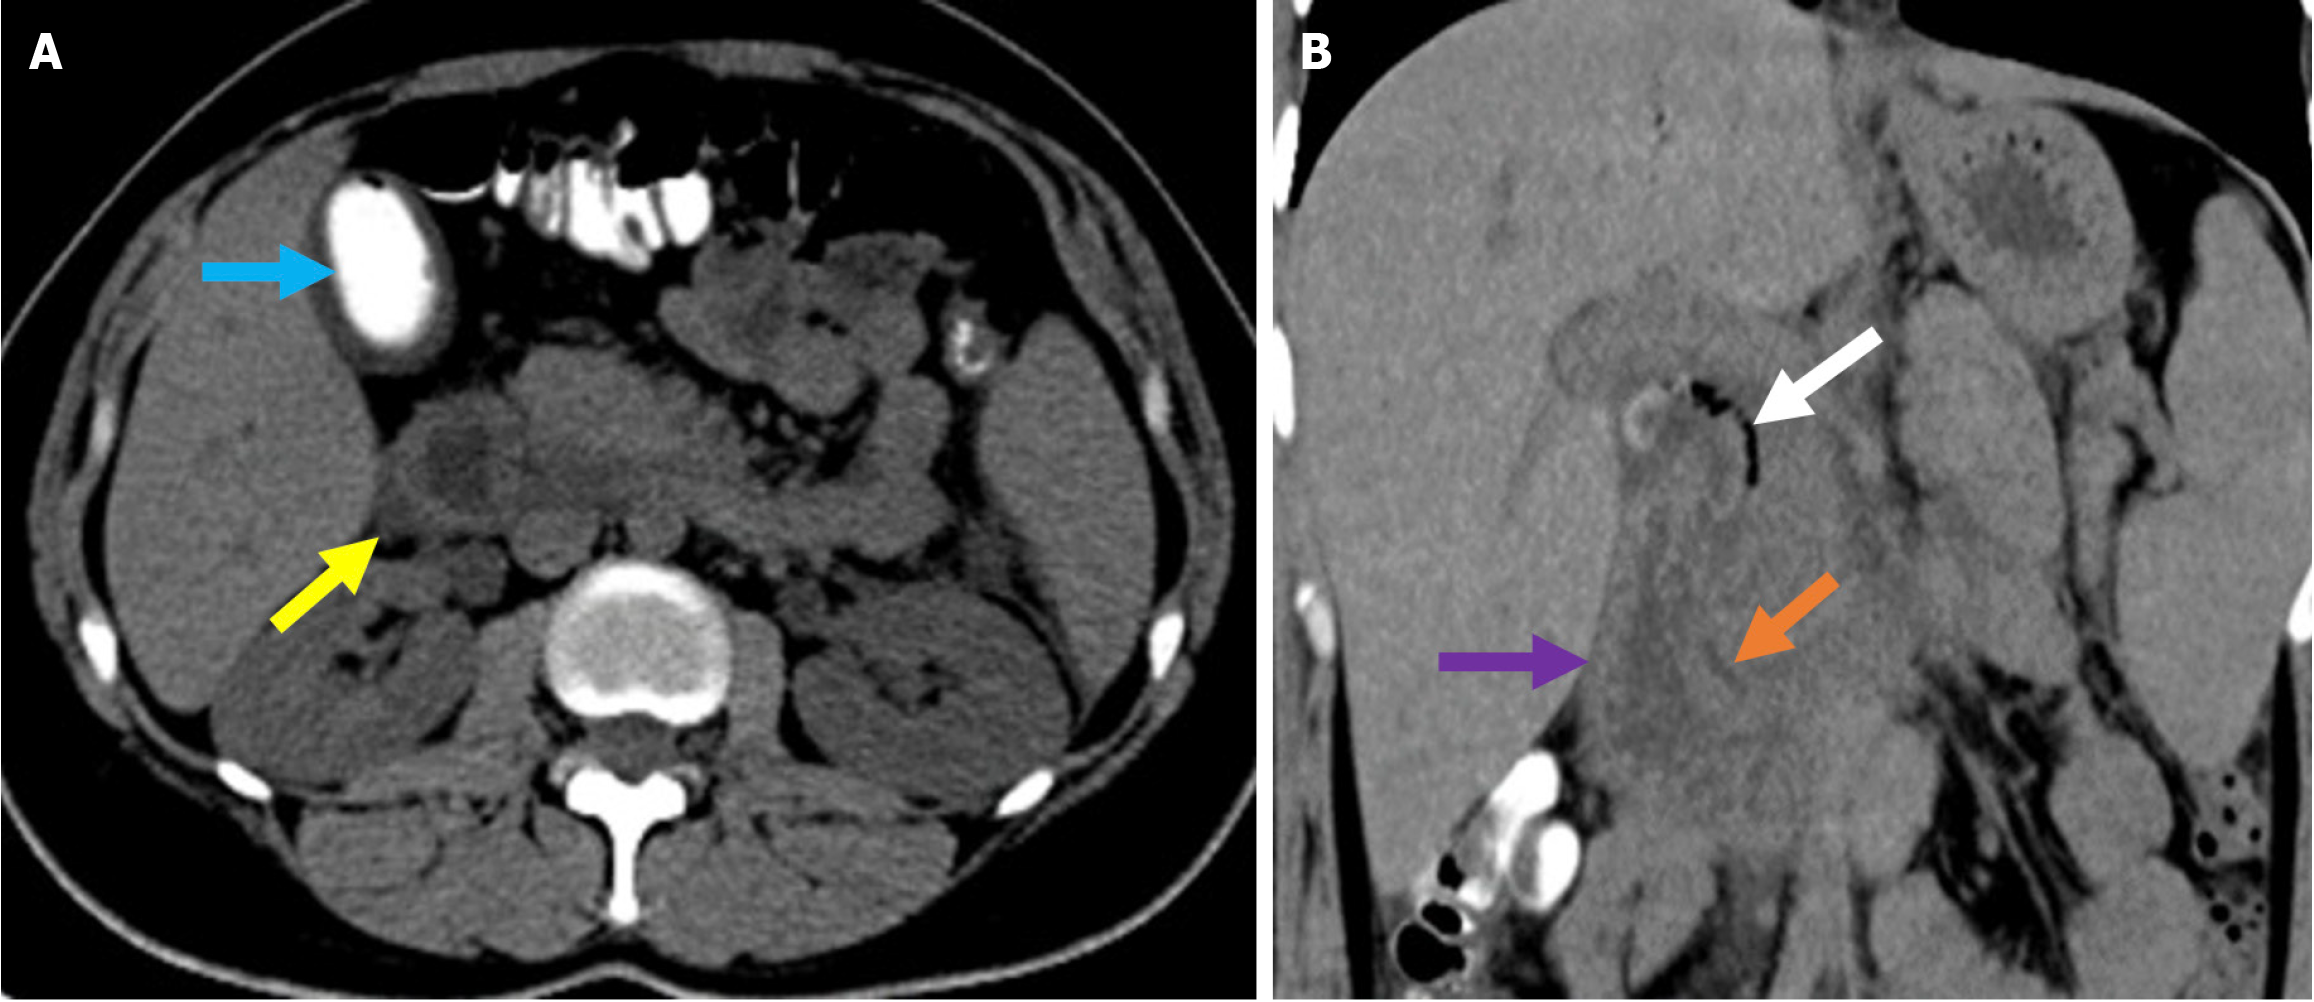

Distal migration of a biliary stent typically involves passage through the gastrointestinal tract without complication. However, there is the potential for perforation of the duodenum, jejunum, ileum, cecum, or colon[83]. Biliary stents cause perforation more frequently than pancreatic stents when migrating distally and may be related to the steeper exit angle of biliary stents into the duodenum[84]. These types of perforations are not included in the Stapfer classification nor other ERCP-related perforation systems. They present with pneumoperitoneum or retroperitoneal gas accumulation, fluid collections, or direct evidence of duodenal wall disruption on abdominal CT. While there are no specific guidelines for the management of stent-related perforations, imaging findings and the patient’s clinical status are critical for determining the appropriate intervention (i.e. surgical or endoscopic) (Figure 18)[79].

Figure 18

Figure 18  Distal stent migration and duodenal perforation. A and B: Coronal (A) and sagittal (B) contrast-enhanced computed tomography images in a 77-year-old female patient with a history of endoscopic retrograde cholangiopancreatography and biliary stenting for cholangitis, who presented with severe abdominal pain. Tachypnea and agitation were observed and were accompanied by nausea, fatigue, and impaired oral intake. Laboratory tests revealed elevated leukocyte counts, C-reactive protein levels, and lactate levels. The stent was found to have migrated distally into the duodenum and perforated the distal portion of the second part of the duodenum (yellow arrow). High attenuation-free fluid, suggestive of hemorrhage, was observed in the perihepatic region and mesentery (blue arrows). The liver exhibited heterogeneous contrast enhancement, consistent with impaired perfusion that was likely related to ischemia (orange circle). Emergent surgical intervention was required.